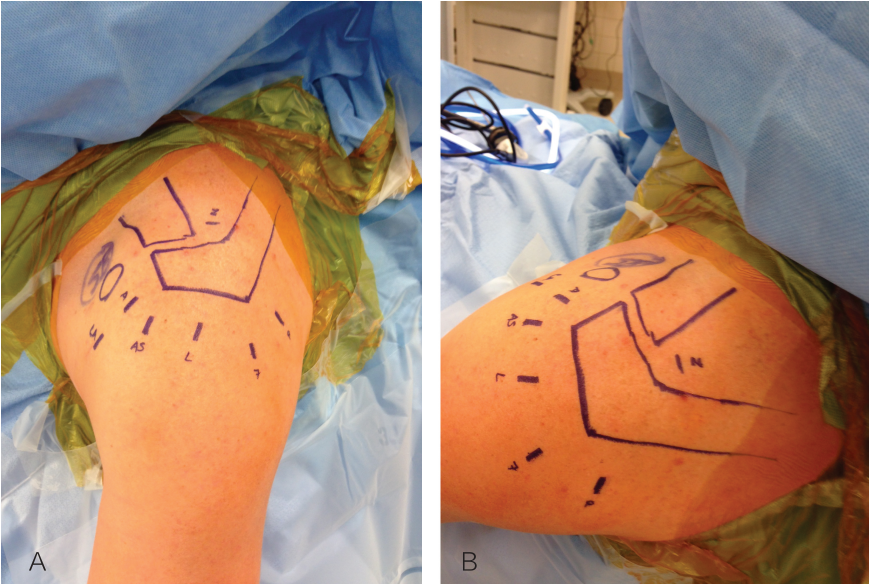

创建前方和后方入路时,与关节盂面成恰当角度,以便锚钉的置入。 高位和外侧放置前方入路可以有效地进行单纯上盂唇的修复。该入路位于肩袖间隙的高位和外侧,用腰椎穿刺针进行定位。非刚性套管有助于在肱二头肌腱附着部后方置入锚钉。 可用于 SLAP 修复的辅助入路包括 Wilmington 入路(肩峰后外侧角前方、外侧各 1 cm 处)或 Neviaser 入路(锁骨、肩峰、肩胛冈组成的三角形内,肩峰内侧 1 cm 处)。